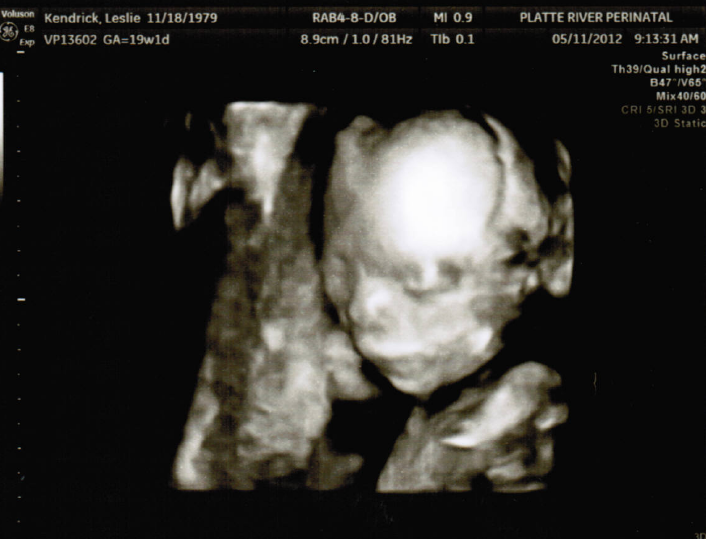

It’s a Boy ... and a Boy!

The babies and mom are about as healthy as can be! Boy B is a little bit bigger than Boy A, but they are both in healthy ranges. Obviously we are thrilled and can now begin the task of picking names.